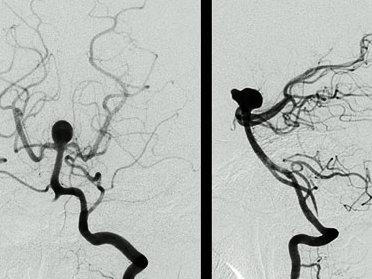

该中心收集了2008~2013年66例患者(其中33例BTAs,33例其他动脉瘤)的CT血管造影(CTA)影像,利用3D-Slicer软件进行了动脉瘤三维模型及周边血管几何形态学参数(包括血管的直径,血管与血管间的夹角等)的测量。在修正了其他形态学参数及临床变量的基础上,多元回归分析显示两侧大脑后动脉间的夹角增大(OR=1.04;P=1.42×10-3)以及基底动脉的直径变小(OR=0.23;P=0.02)都与BTAs的形成密切相关。

临床资料统计表明,基底动脉瘤组与非基底动脉瘤组间影响动脉瘤发生发展的风险因素包括患者的年龄、性别、高血压病史以及吸烟史均差异无统计学意义,而患者的家族史在BTA组中显著高于非BTA组,这两组间差异有统计学意义(P=0.01)(表1)。两组基底动脉的直径、大脑后动脉P1段的直径差异无统计学意义,而大脑后动脉P1-P1角差异有统计学意义(P=1.31×10-5)。

单变量分析表明,基底动脉瘤的形成与更小的基底动脉直径以及大脑后动脉P1段直径间更大的差异有相关,但这些相关性差异无统计学意义。多变量分析表明,更小的基底动脉直径与更大的P1-P1角与基底动脉瘤形成密切相关(表3)。

颅内动脉瘤形成的原因有遗传、不良生活习惯以及血管解剖形态、构造等综合性因素共同构成。而其中血管壁组织结构,血管解剖形态形成的血流动力学改变在动脉瘤的形成中扮演着重要角色。本篇作者通过在CTA影像上测量基底动脉直径以及双侧大脑后动脉之间夹角发现更小的基底动脉直径及更大的双侧大脑后动脉之间夹角与形成基底动脉顶端动脉瘤形成密切相关。从而认为这是一种简单、快捷排查基底动脉瘤高危患者及风险评估的方法。